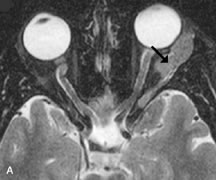

MRI is an excellent modality for demonstrating enlargement of the cavernous sinus and dilation of the superior ophthalmic vein in patients with high-flow carotid-cavernous fistulas (Fig. 14).37MRA may be helpful in the evaluation of the venous outflow pattern. The rapidly flowing blood in these vascular structures carries the excited protons out of the section before they can be imaged, resulting in their dark appearance.5 In low-flow dural arteriovenous malformations, MRA may help define the arterial feeding vessels.45

Fig. 14. Patient with Ehlers-Danlos syndrome who presented with abrupt onset of severe proptosis. A-C. Postcontrast fat-suppressed T1-weighted MR scans demonstrate marked proptosis and engorgement of the extraocular muscles and superior ophthalmic vein (arrows). D. T2-weighted scan through the cavernous sinus demonstrates enlargement and arterialized flow void within the right cavernous sinus (open arrow).